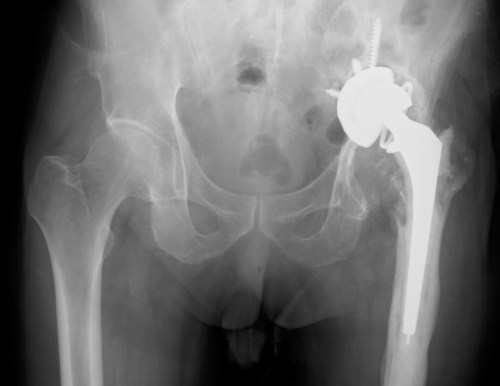

An interesting X-ray. The patient, who is in the later part of the 8th decade of life, but otherwise walking independently at home, had a hip implant following an accident 6 years ago. Had recurrent left hip pain with multiple hospitalisations. Questions: What is the likely diagnosis and how should this elderly patient be managed? [Updated […]